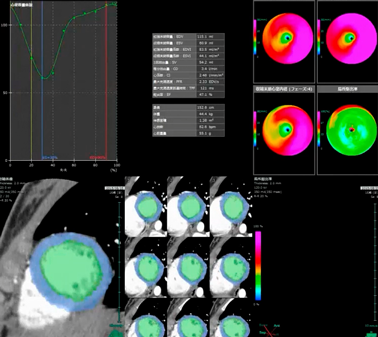

運動負荷心筋シンチグラフィ(201TI)

運動負荷により胸痛が出現し,シンチグラフィで左室前中隔に灌流欠損(perfusion defect;PD)を認めた(Fig. 3A, B).また,安静後は周辺部のPDは改善しているものの中心部にPDの残存を認めた.心筋カウント最低値は55%であった.

Pediatric Cardiology and Cardiac Surgery 33(3): 259-264 (2017)

Fig. 3 Exercise thallium-201 myocardial scintigraphy shows perfusion defect in the anteroseptal wall during exercise (A). It persists after taking a rest (B). Resting thallium-201 scintigraphy (C) and 123I-BMIPP (D) scintigraphy also demonstrate perfusion defect in the anteroseptal wall.

安静時2核種心筋シンチグラフィ(201TI+123I-BMIPP)

後日,運動負荷なしで2核種心筋シンチグラフィを施行した.結果は201TI, 123I-BMIPPともに左室前中隔での取り込み低下(201TI<123I-BMIPP)を認めた(Fig. 3C, D).

冠動脈造影で表在冠動脈に狭窄および攣縮の所見がなく,心筋シンチグラフィで心筋虚血(梗塞と混在)を認めたことから微小血管狭心症と判断した.2015年8月からatenolol 50 mg分1内服を開始した.その後も症状は改善せず,冬になって胸痛頻度が増加した.同年12月の201TI運動負荷心筋シンチで左室前中隔の虚血の増悪を認めた(Fig. 4A)ため,carvedilol 20 mg分2に内服薬を変更し,部活動を禁止した.その後も胸痛が持続するため2016年2月からdiltiazem 100 mg分1を追加した.その後,胸痛はほとんどなくなり,同年5月の201TI運動負荷心筋シンチで虚血範囲の改善を認めた(Fig. 4B).

Fig. 4 The perfusion defect of exercise thallium-201 myocardial scintigraphy deteriorated despite treatment with atenolol (A). In addition to limiting exercise, concomitant treatment using carvedilol and diltiazem reduced the frequency of chest pain. The perfusion defect showed improvement (B).